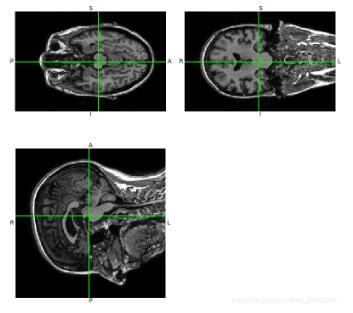

3D顯示結果: